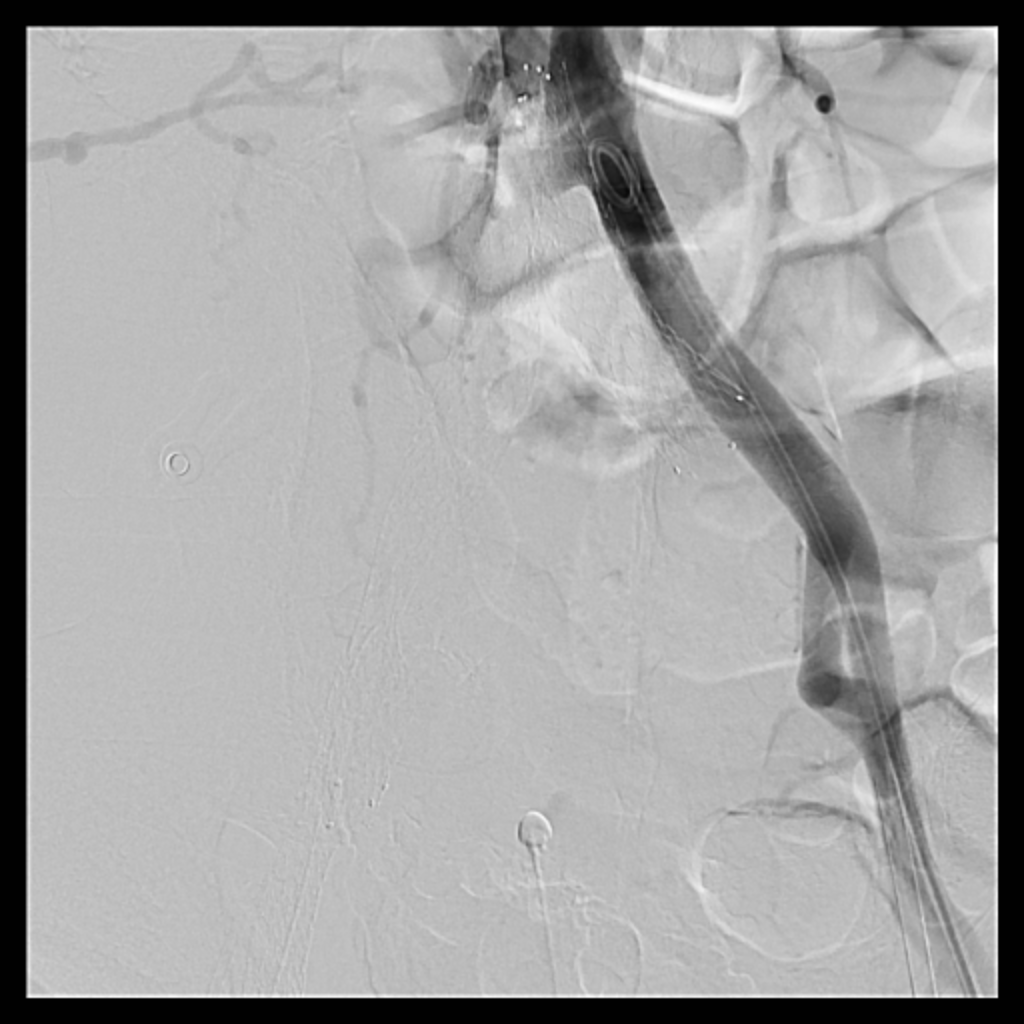

Catheterization revealed total occlusion of the right common iliac artery, likely due to tumor compression. Diffuse thrombosis was seen in the right common femoral vein, with total occlusion from the right common iliac vein to proximal RCFV. LCIV ostial stenosis (~80%) and IVC stenosis (~90%) were also present.

Venous access was obtained and venography confirmed heavy thrombus burden; therefore, the initial 6 Fr sheath was upsized to a 9 Fr sheath. Two Terumo stiff wires were advanced into the IVC to secure stable access. Mechanical thrombectomy using the Boston Scientific AngioJet system was performed from the right iliac vein to the right common femoral vein. During venography, unexpected early arterial opacification suggested an iatrogenic artery-to-vein fistula. Iliac angiography was then performed, revealing a total occlusion of the right common iliac artery with collateral reconstitution. To restore arterial flow and seal the fistula, a contralateral approach was used. A wire successfully crossed the occluded segment into the true lumen, followed by deployment of a covered stent. Final angiography showed complete closure of the fistula and restored antegrade arterial flow without distal embolization. The patient remained hemodynamically stable.